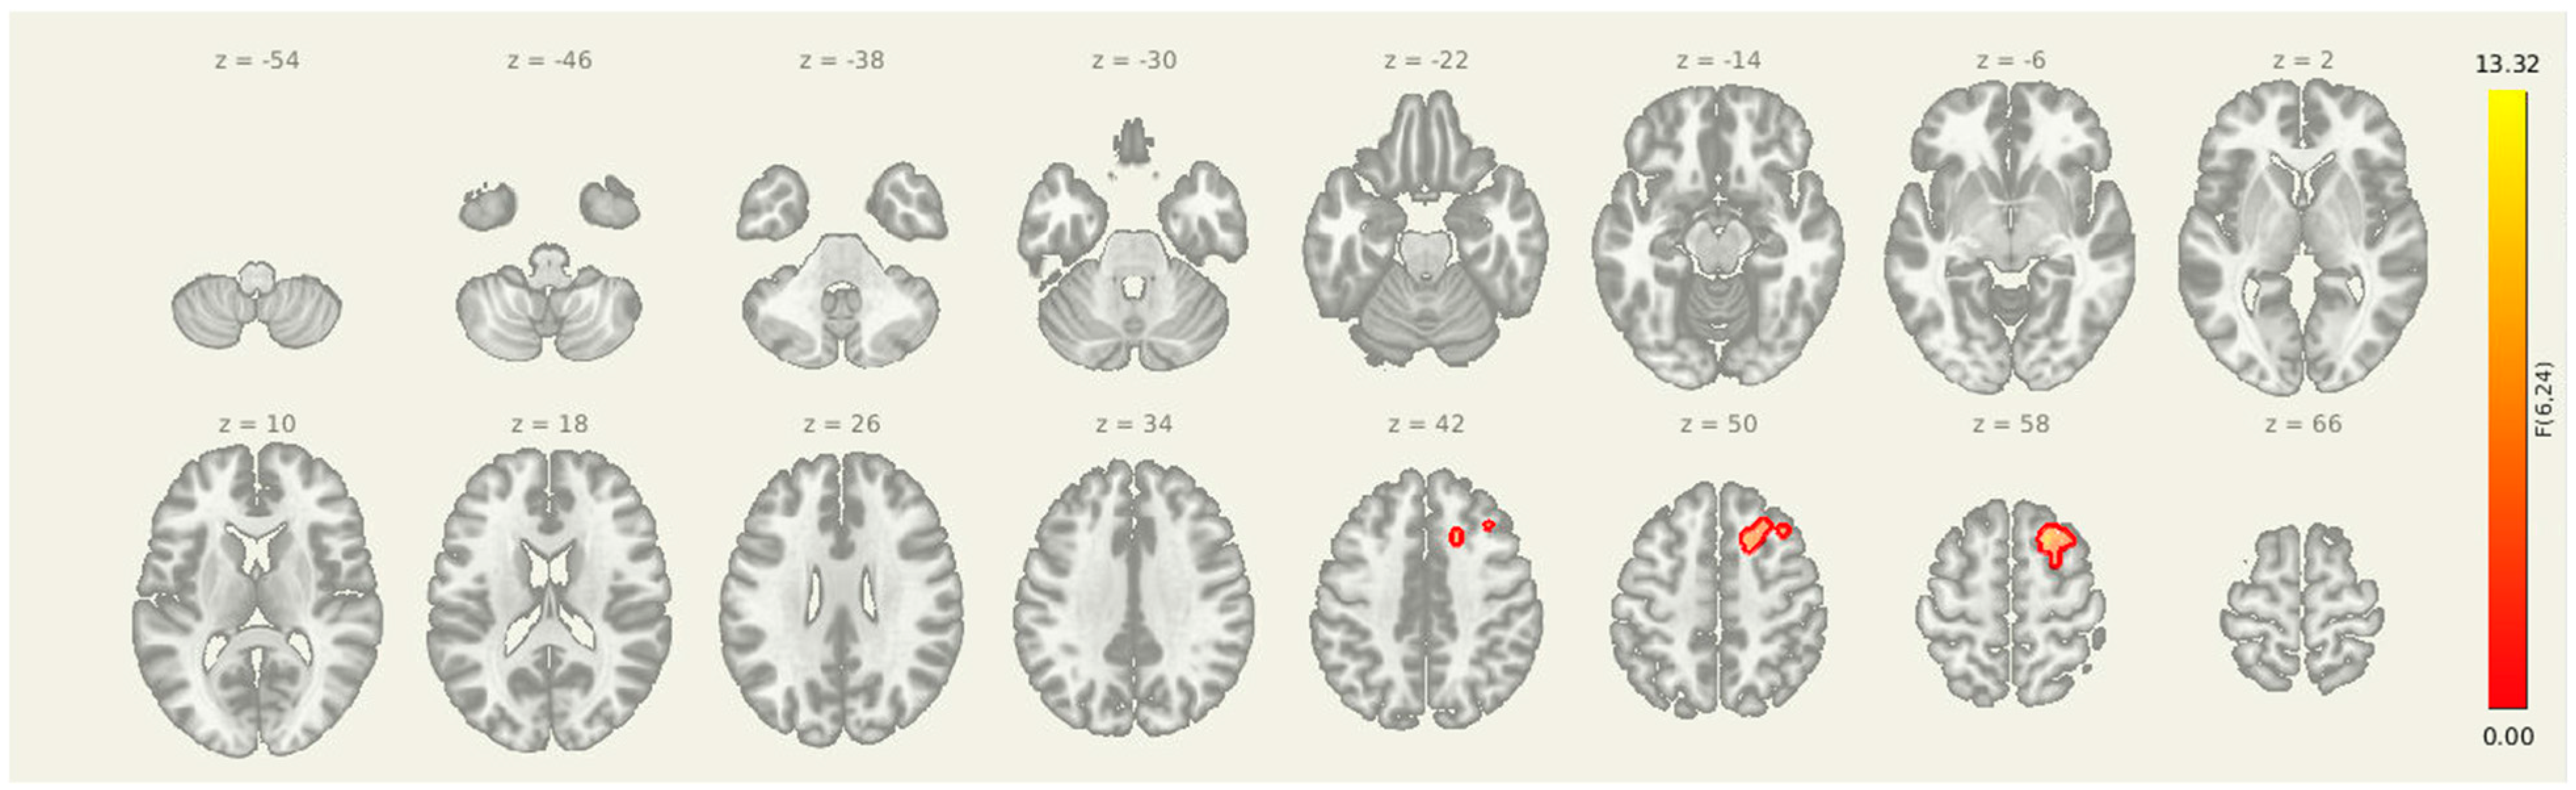

3.5. Amygdala-Insula-Thalamus Seed

Seeding from amygdala-insula-thalamus (Figure 4 and Table 6) revealed a significant post-intervention reduction in connectivity from the insula, amygdala, and thalamus to a cluster in the right superior frontal cortex (MNI coordinates: +20, +18, +56; cluster size = 133 voxels; p-FDR = 0.0065). These results suggest that improved prefrontal oversight may be a key mechanism through which the intervention alters pain-related brain dynamics in individuals with post-stroke headache.

Figure 4.

Post-intervention reductions in connectivity from limbic seed regions. Significant decreases in seed-to-voxel connectivity were observed from the amygdala, insula, and thalamus following the intervention. Clusters included sensorimotor, frontal, and subcortical regions. Results are thresholded at p-FDR < 0.05.